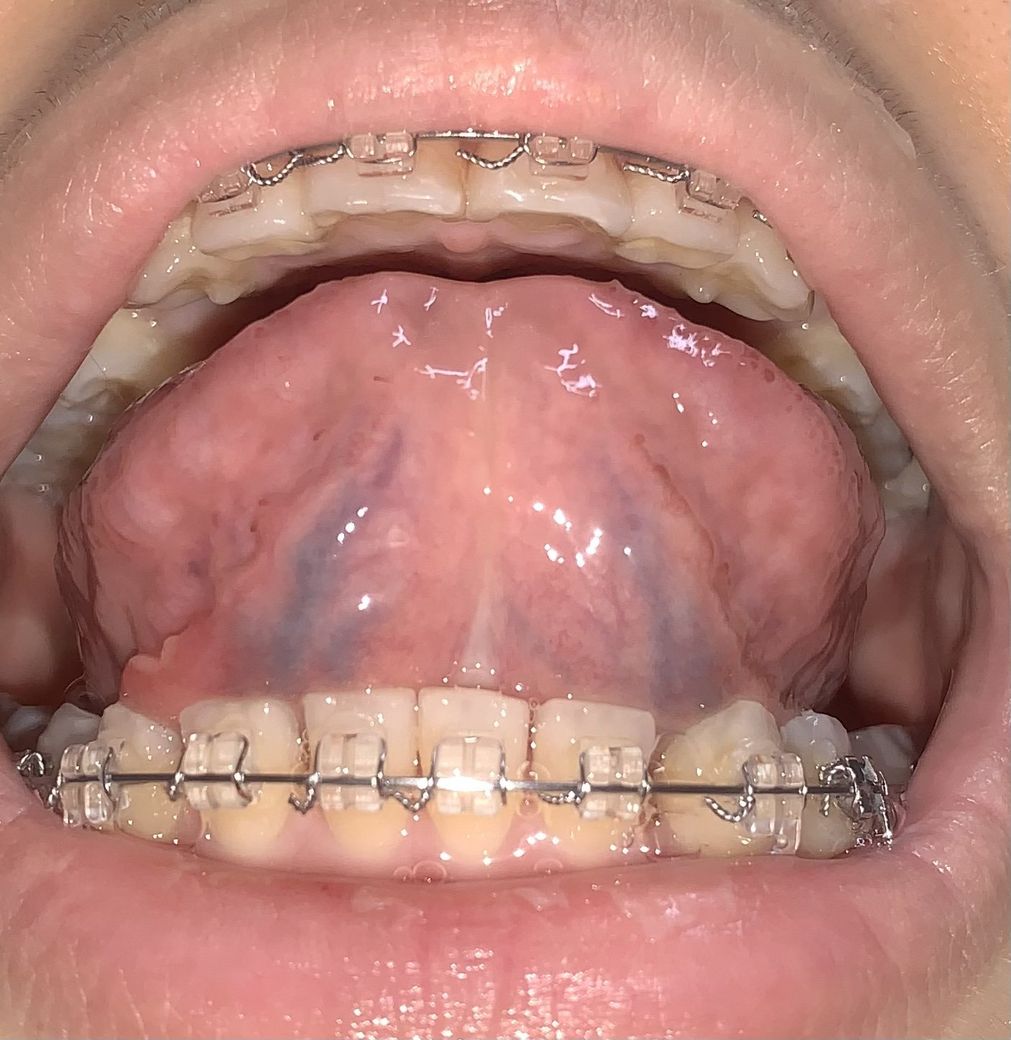

사진 에서 보다시피 혀 아래 왼쪽 부분이 울퉁불퉁하게 패이고 뭐가 낫어요..

만지면 아프고 가만히 입을 다물고 있어도 아픕니다. 원인이 뭘까요,,?? 병원에 가봐야 하나요? 알려주세요~!! ㅠㅠ

질문하신 내용에 대하여 아래와 같이 답변 드립니다.혀 아래 바깥쪽 부분 점막이 반대편보다 약간 울퉁불퉁하게 부어있군요.

구강안을 직접 보지 않아 정확치 않지만 하마종(ranula)의 가능성이 있습니다.

질문하신 내용에 대하여 아래와 같이 답변 드립니다.사진으로 봤을 때 왼쪽 아래에 구내염이 있는것으로 보입니다.

아프타성 구내염으로 보이는데, 씹는 상처, 스트레스, 피곤할 때 생길 수 있습니다.